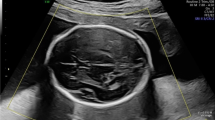

In comparison with standard two-dimensional (2D) imaging of fetal structure and biometry, we aimed to evaluate the role of three-dimensional (3D) imaging as a screening tool in the mid-trimester.

Pregnant women presenting between 18and 22 weeks for routine anatomical survey and biometric measurements were recruited. Six volumes of fetal anatomic regions were obtained and archived for later reconstruction, along with three volumes of extra-fetal structures (placenta, cervix, amniotic fluid). The 2D standard fetal images were then obtained. Offline reconstruction of 3D volumes was performed for comparative analysis (2D vs 3D). Subsequently, 3D volumes were reconstructed to mirror traditional 2D and allow biometric comparison between the two techniques. Data of 98 patients were analyzed.

Complete visualization of vital anatomic structures was seen ⩾85% of the time with 3D ultrasound. The 3D imaging improved the assessment of the four heart chambers (P=0.003), thoracic spine (P=0.008) and lumbar spine (P=0.012) views. The 2D imaging was superior for the fetal head, placenta and upper limbs. Conditional probabilities were used to assess the clinical value of 3D when standard 2D views were incomplete (mean 0.8830; 95% confidence interval 0.8059 to 0.9320). Overall diagnostic accuracy of 3D ultrasound is not superior for all fetal anatomic structures. Fetal biometric measurements assessed by both techniques demonstrated substantial to excellent agreement.

The use of 3D imaging as a primary screening tool is limited and may be best utilized as a second-stage test. Overall, there is good correlation between fetal biometry assessed by either 2D or 3D technology.